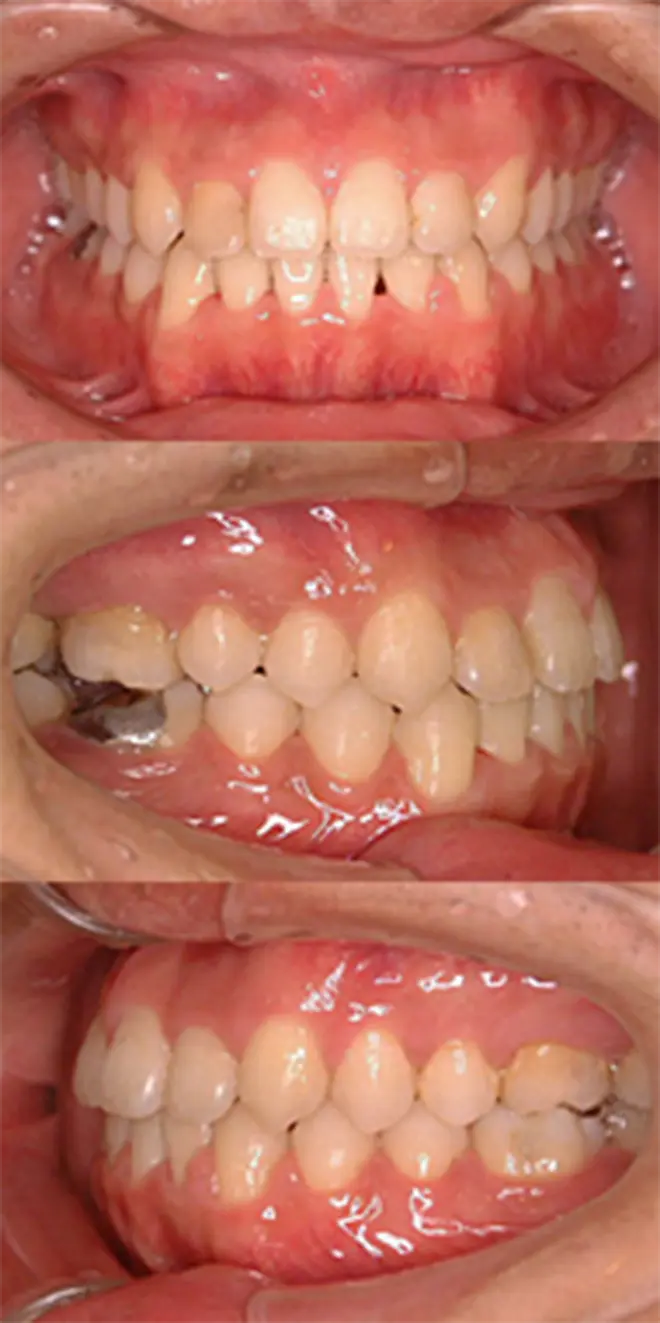

| 患者さまの年齢・性別 | 30代・男性 |

|---|---|

| 治療期間 | 2年2ヵ月 |

| 治療費(税込) | 1,567,500円 |

| 主訴 | ガミースマイルが気になる。 |

| 診断名・主な症状 | 過蓋咬合 |

| 治療に用いた主な装置 | 舌側矯正装置、歯科矯正用アンカースクリュー |

| 治療内容 |

歯科矯正用アンカースクリューにより上顎前歯を上方と後方に移動させ、ガミースマイルと上顎前突の改善を行ないました。 |

| 抜歯部位 | 非抜歯 |